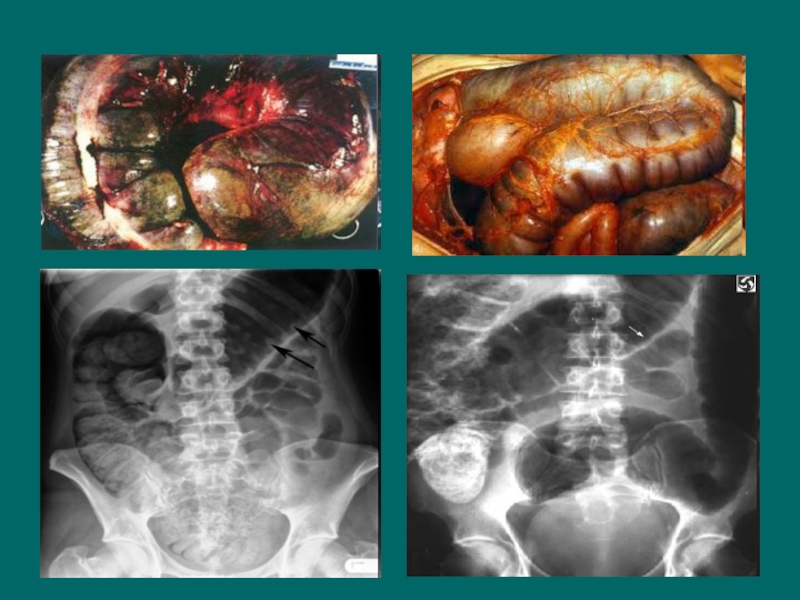

Слайд 34Осложнения

Массивные кишечные кровотечения встречаются у 1-6% больных ЯК и

редко при БК. Стриктуры и стеноз кишки - у 30-50%

пациентов с БК и реже - у 7-11% с ЯК.

Перфорация кишки более характерна для ЯК.

Острая токсическая дилатация толстой кишки (токсический мегаколон)

Свищи (фистулы) характерны для БК (отмечаются у 26-48% больных) и редко при ЯК.

Абсцессы чаще сопровождают свищи и бывают перикишечные, тазовые и печёночные.

Синдром нарушенного питания и всасывания - у 75-80% больных с БК и у 5-10% при ЯК.

Тромбоэмболические осложнения встречаются достаточно редко.

Дисплазия и рак. При БК частота развития рака кишечника несколько выше, чем в общей популяции, но значительно ниже, чем при ЯК.

Осложнения Массивные кишечные кровотечения встречаются у 1-6% больных ЯК и редко при БК. Стриктуры и стеноз кишки

Слайд 36Перфорация

Перфорация